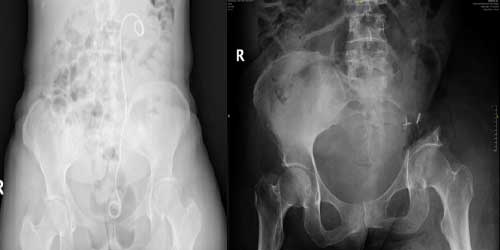

Omurga metastazı, kanserin ilk olarak iç organlarda gelişip daha sonra omurga kemiklerine yayılması sonucu oluşan bir durumdur. Çoğunlukla kan yoluyla sıçrayan bu tür metastaz, hastalarda sırt ve bel ağrısı gibi şikayetlerle kendini gösterir. Erken teşhis ve uygun tedavi yöntemleri, hastaların yaşam kalitesini artırmada kritik bir rol oynar.

Tedavide başarıyı artıran en önemli etkenlerden biri ameliyat öncesi iyi bir hazırlık ve cerrahi planlama yapmaktır. Her şeyden önce tanı doğru konmalı. Bunun için hasta iyi dinlenip, detaylı muayene edildikten sonra tetkikleri dikkatli incelenmelidir.